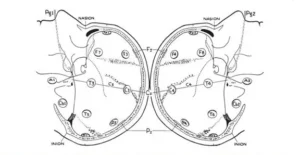

A circumferential measurement (fig.3) is then taken over the temporal lobes from the midline Fp position to the midline O position.

A mark is made at 10% of this measurement indicating the left or right Fp electrode position. Marks are then made at 20% of the measurement and are labeled inferior frontal, mid-temporal, and posterior temporal and left or right occipital (note that the mid-temporal electrode positions are crossed). The remaining 10% measurement from the left and right occipital marks would be the midline = position. Variations of this measurement have been described by Harner and Sannit (1974)

Fig.3 Superior view with cross section of skull through the temporal line of electrodes illustrating the 10-20 system applied in this direction as described in the text